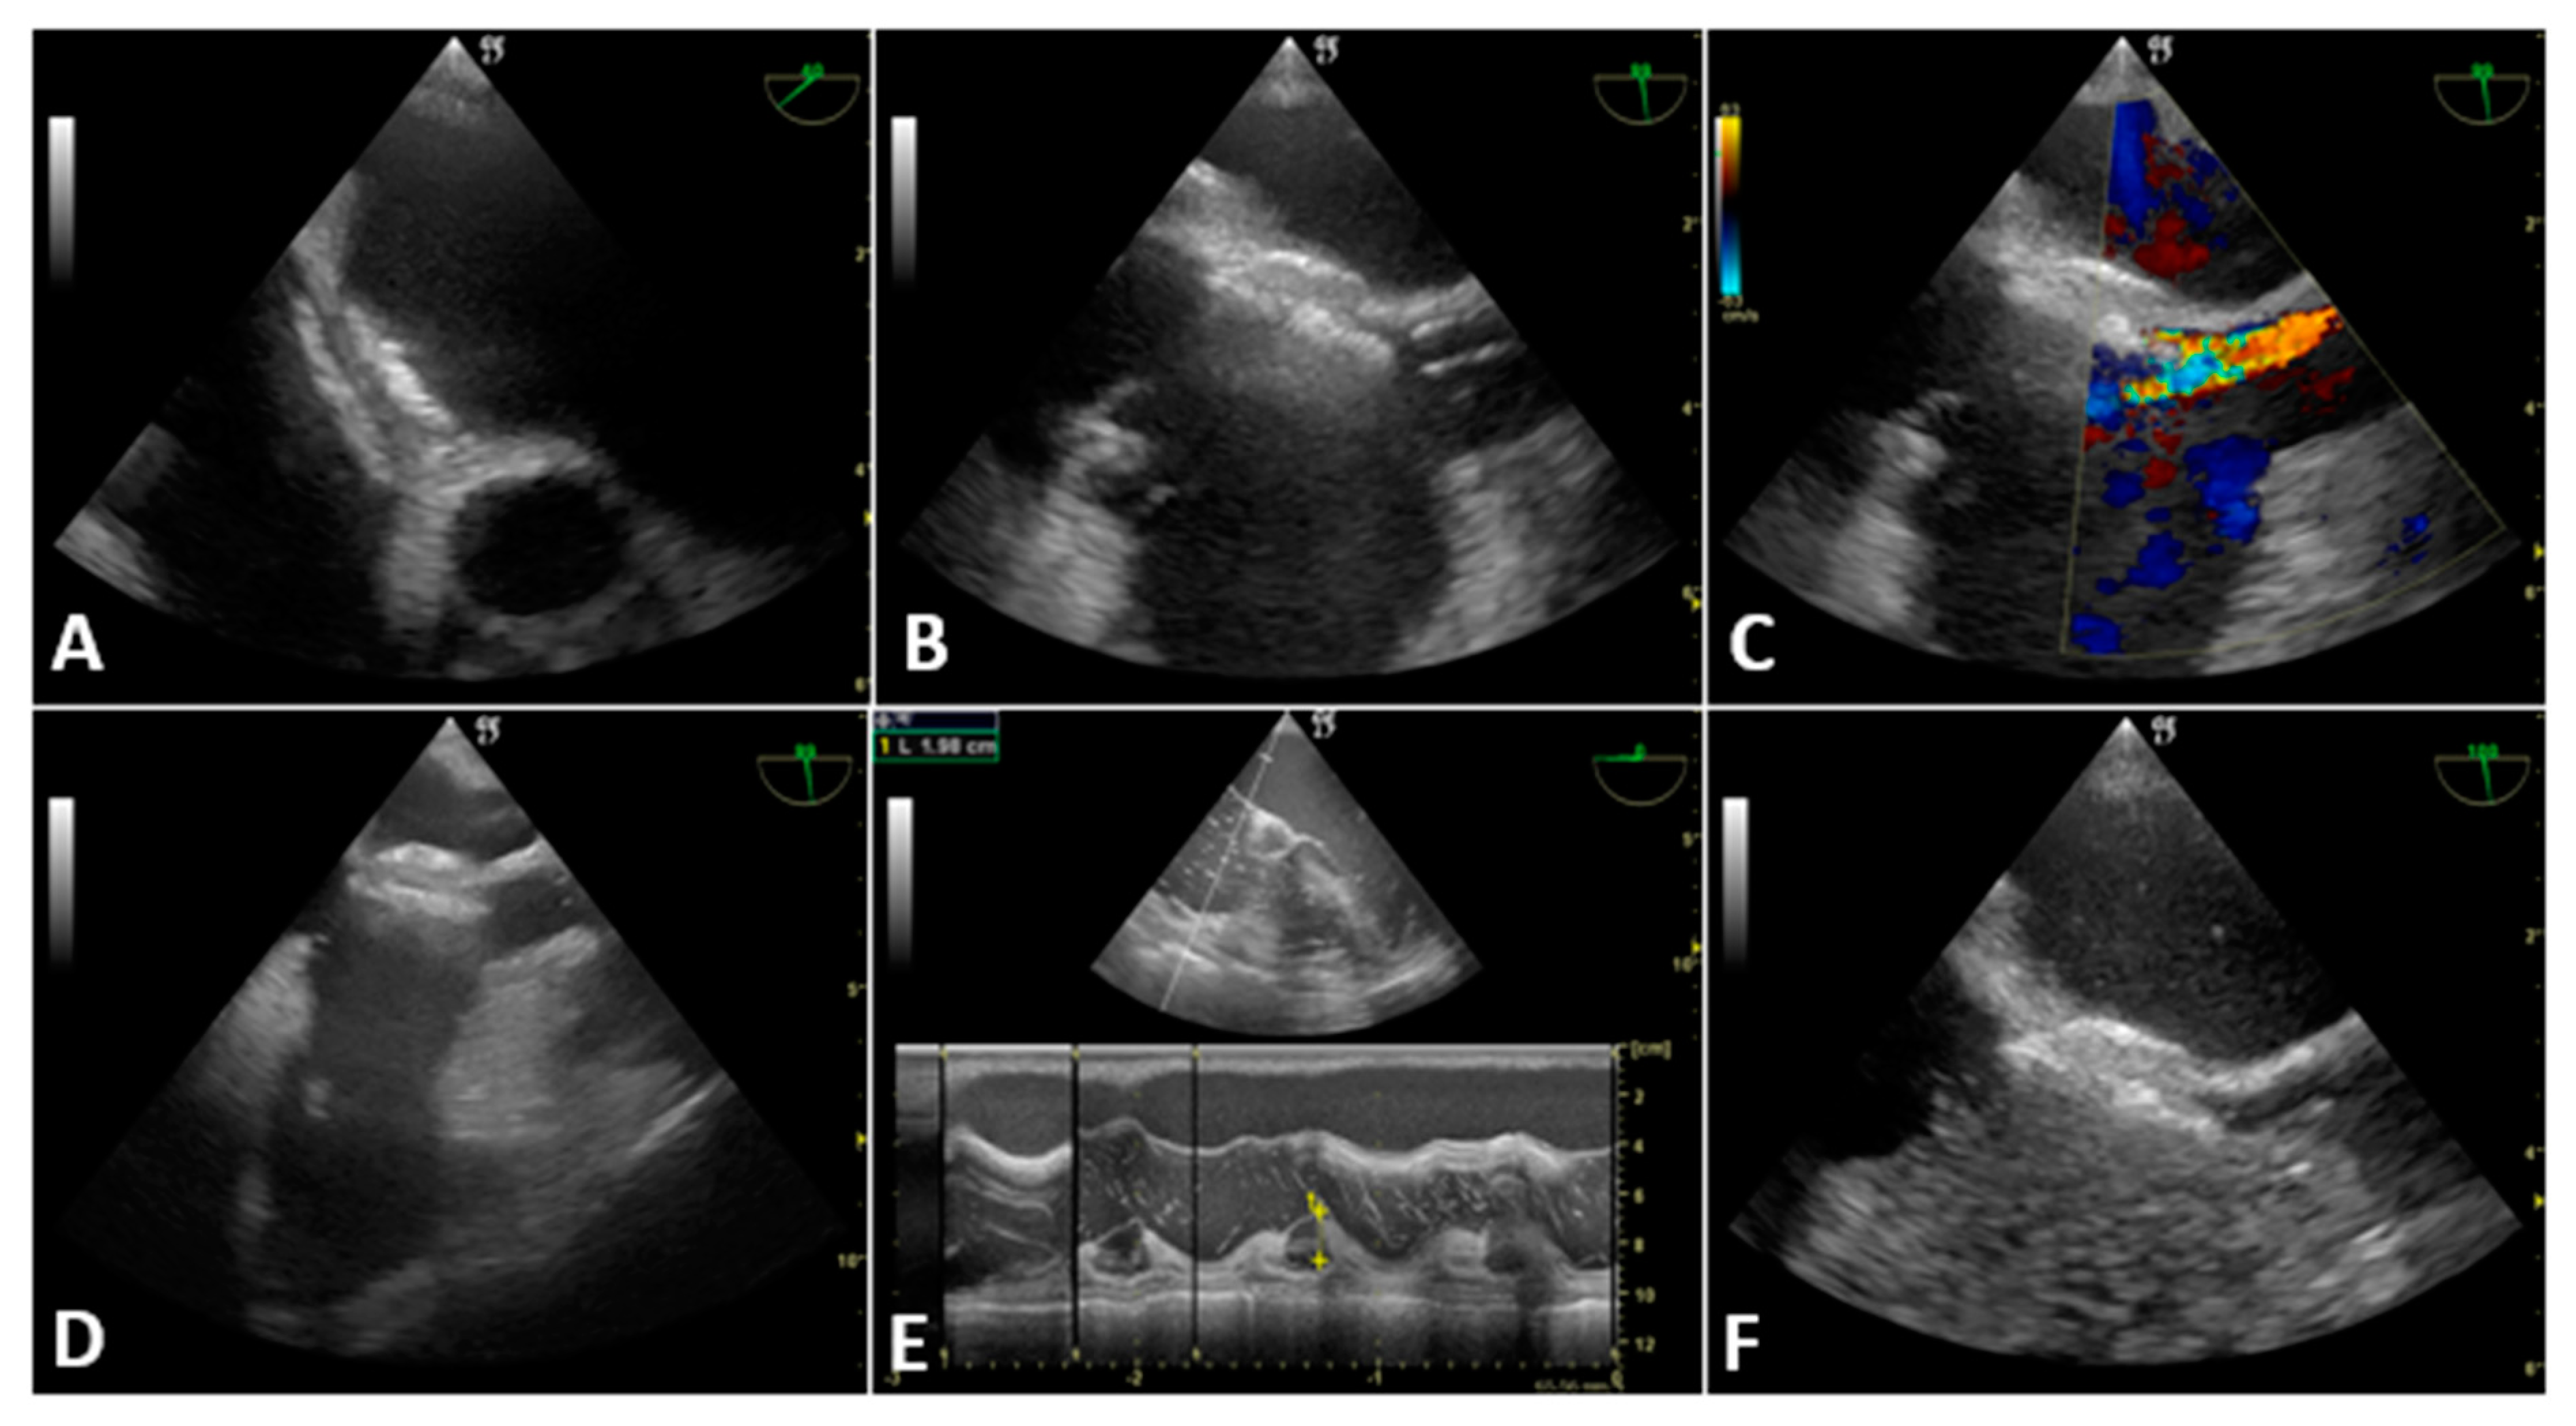

3.2.1. Case 1

3.2.2. Case 2

3.2.3. Case 3

3.2.4. Case 4